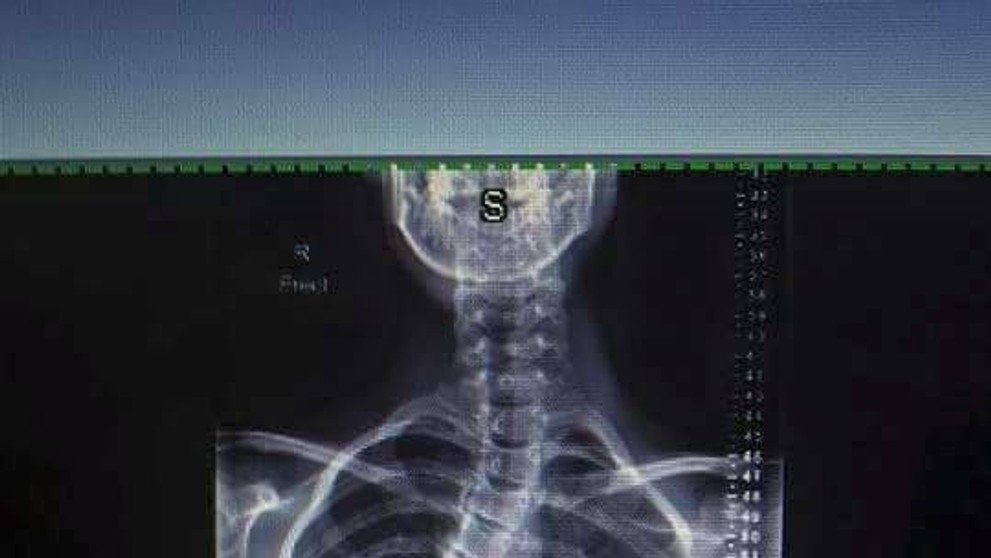

Dievča trpí vzácnou chorobou. Chrbticu mala o 55 stupňov vykrivenú

Sam Hansen a jej chrbtica predtým a teraz.

Mladá Novozélanďanka Sam Hansen má vzácnu chorobu. Ide o idiopatickú skoliózu. Chrbticu mala vykrivenú o 55 stupňov. Prvýkrát si to všimla, keď mala dvanásť rokov a chcela sa zohnúť pre niečo na zemi. Rodičia si všimli, že jej zvláštne trčia rebrá. Začala nosiť veľké a rozťahané veci, aby to zakryla.